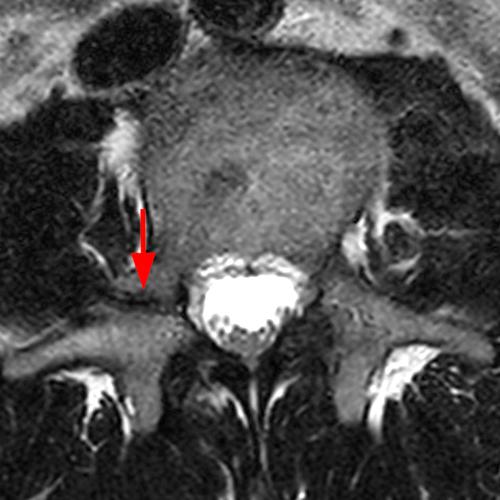

Case 1: T2-weighted axial (3A) and sagittal STIR (3B) sequences show marked cortical T2/STIR hyperintensity in the left pedicle of L5 surrounding a hypointense line (arrows) which begins at the inferior/medial margin of the pedicle and nearly completely traverses the pedicle.

Case 1: Acute left-sided pediculolysis